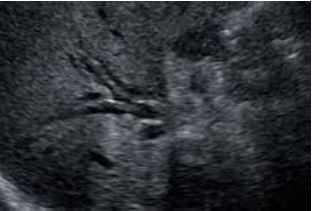

Холангіокарцинома

При оцінці ступеня інфільтрації холангіокарциноми на 3D-реконструкціях неможливо візуалізувати суцільність жовчної протоки на одному зображенні в С-площині (рис.5б). Однак, простеживши додаткові точки в просвіті і відобразивши їх за допомогою Curved MPR, можна сформувати вигнуту С-площину. У вигнутій С-площині (рис.5в) можна чітко візуалізувати безперервність жовчної протоки, що дозволяє легко оцінити ураження та прилеглі ділянки. Крім того, Shadow Glass (Рис. 5г) дозволяє відобразити задню стінку, що дає змогу чіткіше спостерігати за всією структурою жовчної протоки.

а) А-площина

б) Звичайна С-площина

в) Вигнута С-площина (OmniView)

г) Shadow Glass

Рисунок 5. Діагностика холангіокарциноми за допомогою Smart Sensor 3D